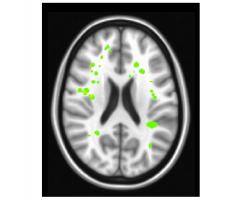

L’étude est basée sur des expériences menées avec 18 femmes et 10 hommes volontaires en bonne santé invités à accomplir des tâches visant à exercer leur mémoire alors qu’ils passaient une IRM fonctionnelle. L’équipe observe, en cas de fatigue mentale, une augmentation de l'activité dans 2 zones du cerveau qui interagissent pour réagir, et peut-être réguler, le cerveau lorsqu'il se sent fatigué et lorsqu’il cesse ou poursuit son effort mental.

Globalement, les résultats des tests ont révélé une augmentation de l'activité et de la connectivité dans ces 2 zones cérébrales lorsque les participants ressentaient de la fatigue cognitive :

- l'insula droite, une zone cérébrale profonde associée à la sensation de fatigue,

- le cortex préfrontal latéral dorsal,

- ces 2 zones étant situées de part et d'autre de la région du cerveau qui contrôle la mémoire de travail ;

- chez chacun de ces participants, l'activité dans les 2 zones cérébrales pendant la fatigue cognitive a augmenté de plus de 2 fois par rapport aux mesures de base.